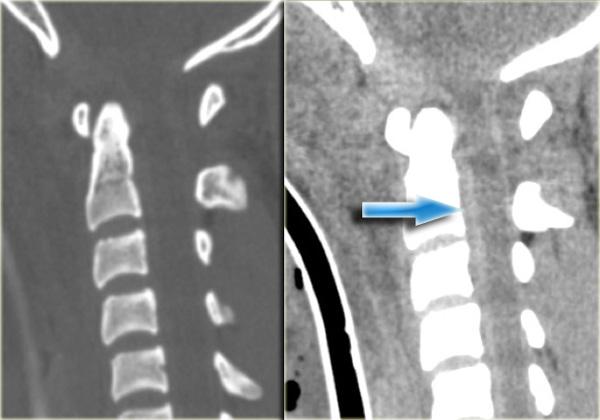

Bên trái là hình ảnh của một phụ nữ 44 tuổi bị ngã trên băng.

Sau đó bà bị ngã lần thứ hai vào sáng hôm sau, và sau đó mất hoàn toàn vận động và cảm giác.

Khám thực thể cho thấy liệt hai chi dưới kèm yếu nhẹ chi trên bên phải.

Ban đầu được đề xuất chẩn đoán tổn thương tủy trung tâm.

X-quang bình thường.

Các dấu hiệu bao gồm:

- Các mảnh xương nhỏ tách ra từ mặt khớp trên và dưới

- Khoang gian gai rộng ra tại C5-6

- Sưng nề mô mềm ở mức này về phía sau

- Hẹp nhẹ khoang đĩa đệm tại mức C5-6.

Các dấu hiệu CT này rất tinh tế và dường như không tương xứng với vấn đề thần kinh.

Trong trường hợp như vậy, MRI là bước tiếp theo cần thực hiện.

Đầu tiên chúng tôi trình bày hình CT mặt phẳng coronal và axial với cửa sổ mô mềm.

Có vật liệu tăng tỷ trọng ở phía sau khoang đĩa đệm, rất gợi ý thoát vị đĩa đệm do chấn thương.

Tụ máu ngoài màng cứng cần được đưa vào chẩn đoán phân biệt, nhưng dấu hiệu này chỉ giới hạn ở vùng khoang đĩa đệm, khác với hình ảnh của khối máu tụ.